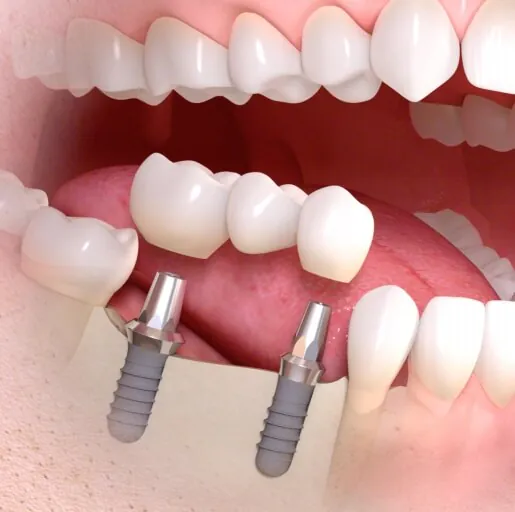

インプラント治療は、歯を失った箇所に人工の歯根(インプラント)を埋め込み、歯を補う治療法です。従来の治療法であるブリッジや入れ歯とは異なり、インプラントを顎の骨に埋め込むことで、優れた安定性を実現します。

インプラント治療は、歯を失った箇所に人工の歯根(インプラント)を埋め込み、歯を補う治療法です。従来の治療法であるブリッジや入れ歯とは異なり、インプラントを顎の骨に埋め込むことで、優れた安定性を実現します。

インプラント治療では、まず歯科医師が顎の骨の状態を評価し、適切なインプラントの種類とサイズを選定します。そして、インプラントを顎の骨に埋め込み、骨とインプラントが結合してから人工の歯冠を取り付けることで、自然な見た目と噛む機能を回復させます。

それに対して、インプラント治療では、健康な歯を利用せずに人工の歯根を埋め込み、人工の歯冠を固定します。これにより、健康な歯を保持しながら咀嚼力を回復させることができます。

それに対してインプラント治療では、複数のインプラントを埋め込んで複数の人工歯を支えることで、安定した嚙み合わせと美しい見た目の歯を手に入れることができます。